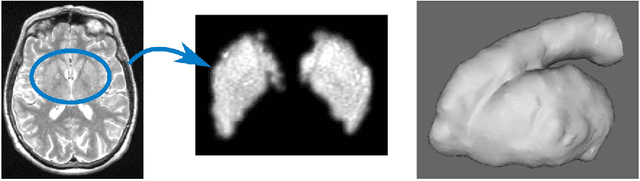

Abstract:Enlarged perivascular spaces (EPVS) in the brain are an emerging imaging marker for cerebral small vessel disease, and have been shown to be related to increased risk of various neurological diseases, including stroke and dementia. Automatic quantification of EPVS would greatly help to advance research into its etiology and its potential as a risk indicator of disease. We propose a convolutional network regression method to quantify the extent of EPVS in the basal ganglia from 3D brain MRI. We first segment the basal ganglia and subsequently apply a 3D convolutional regression network designed for small object detection within this region of interest. The network takes an image as input, and outputs a quantification score of EPVS. The network has significantly more convolution operations than pooling ones and no final activation, allowing it to span the space of real numbers. We validated our approach using a dataset of 2000 brain MRI scans scored visually. Experiments with varying sizes of training and test sets showed that a good performance can be achieved with a training set of only 200 scans. With a training set of 1000 scans, the intraclass correlation coefficient (ICC) between our scoring method and the expert's visual score was 0.74. Our method outperforms by a large margin - more than 0.10 - four more conventional automated approaches based on intensities, scale-invariant feature transform, and random forest. We show that the network learns the structures of interest and investigate the influence of hyper-parameters on the performance. We also evaluate the reproducibility of our network using a set of 60 subjects scanned twice (scan-rescan reproducibility). On this set our network achieves an ICC of 0.93, while the intrarater agreement reaches 0.80. Furthermore, the automatic EPVS scoring correlates similarly to age as visual scoring.